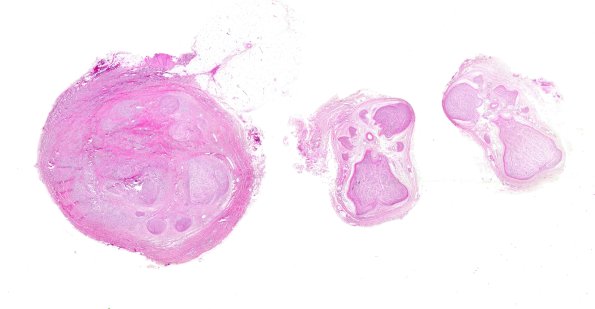

Washington University Experience | PERIPHERAL NEUROPATHY | 19 TRAUMATIC INJURIES | 24A1 Neuroma (Case 24) H&E WM

Case 24 History ---- The patient is a 39 year old male with clinical history of right perineal nerve injury. Operative procedure and findings: exploratory surgery right perineal nerve; right perineal nerve graft using right sural nerve. ---- 24A1-3 H&E stained sections show the presence of normal nerve fascicles followed by chaotic arrangement of a disorganized plexus of axons and Schwann cells within a fibrocollagenous stroma. The fascicles are small and surrounded by delicate perineurial processes (mini-fascicles). (H&E).